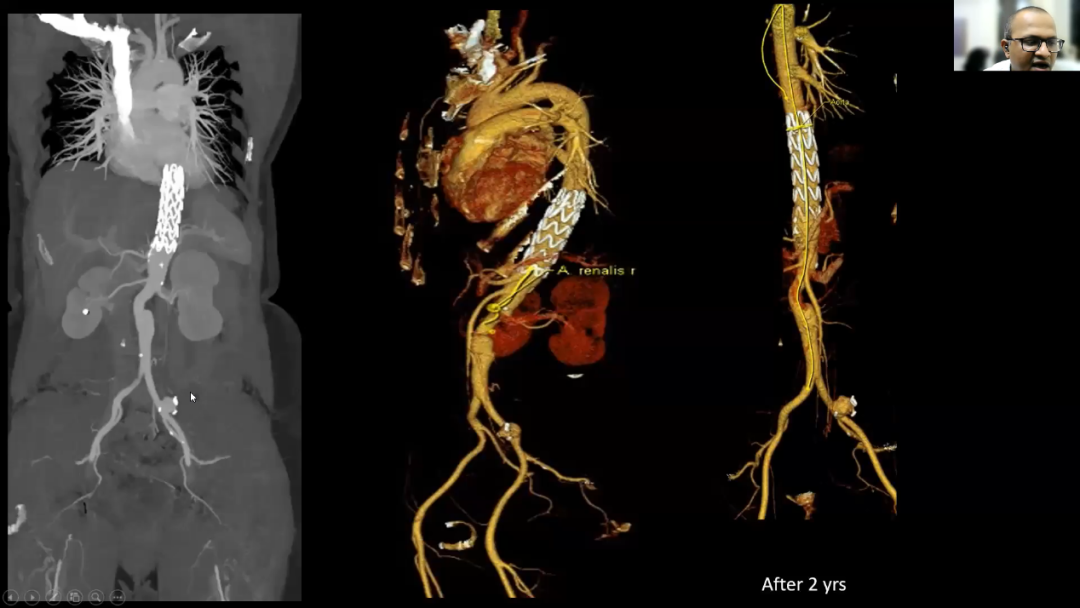

来自印度的Avinash Gutte教授分享了彩神在线网信彩票-彩神通免费版下载-彩神8争霸vlll-彩神购彩购彩大厅-彩神软件陆立根免费版-彩神ll争霸3-彩神ll彩神8-彩神ll争霸彩票-拼搏在线彩神网网页版腔内治疗综合解决方案在应对复杂病变时提供的优秀治疗效果。他强调,彩神在线网信彩票-彩神通免费版下载-彩神8争霸vlll-彩神购彩购彩大厅-彩神软件陆立根免费版-彩神ll争霸3-彩神ll彩神8-彩神ll争霸彩票-拼搏在线彩神网网页版Ankura™胸主动脉覆膜支架的多维锥度设计能有效降低远端再发破口的机率, 可确保患者术后的远期安全及通畅率。